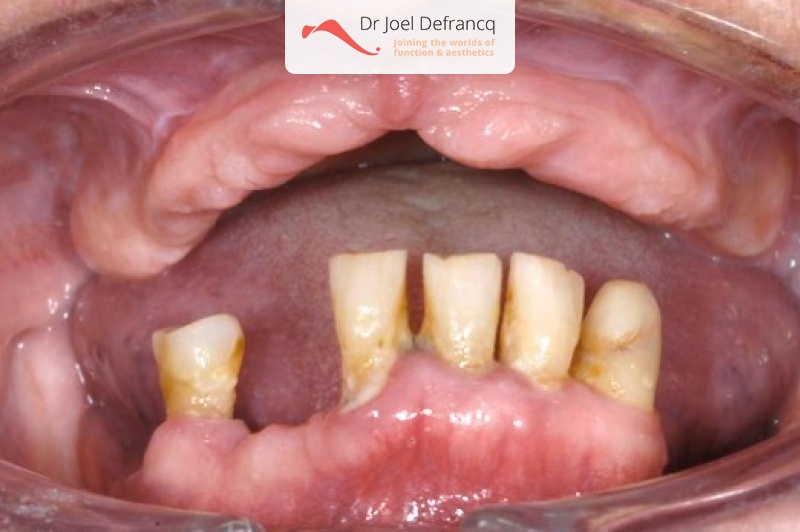

Dentale diagnose

- Open beet

Behandeling tandheelkundige implantaten

- Vaste tanden op implantaten (bovenkaak)

- Vaste tanden op implantaten (onderkaak)